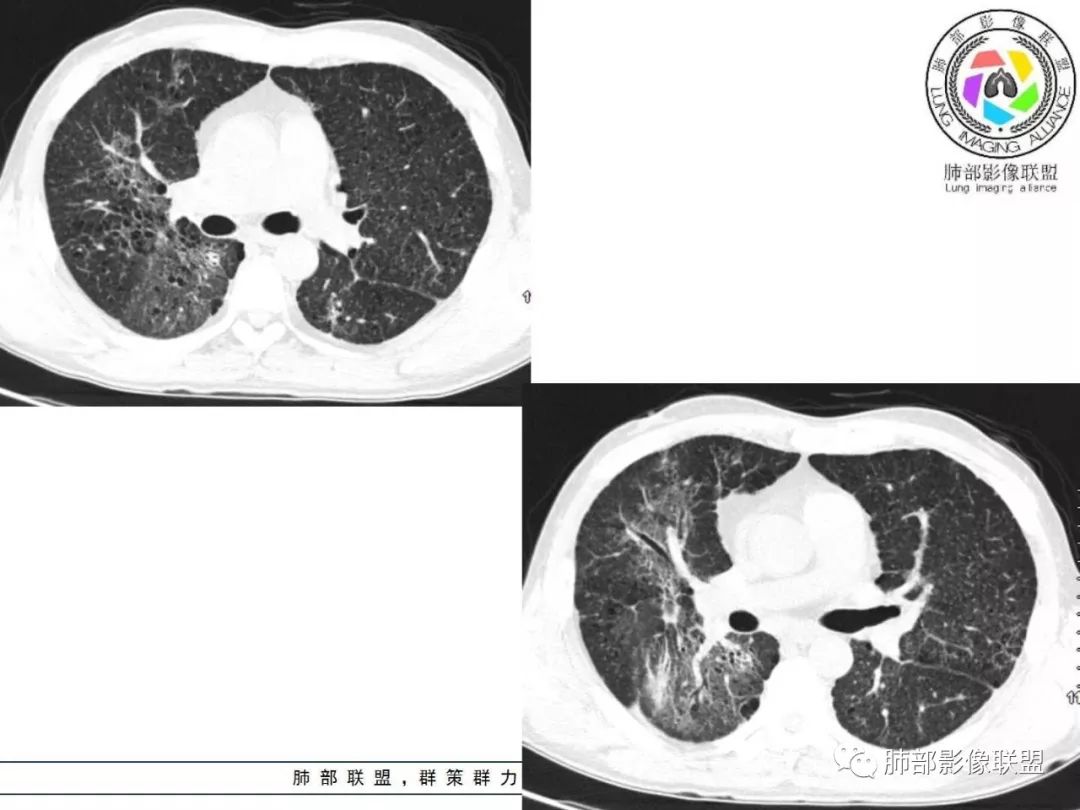

胸部CT:两肺弥漫病灶,磨玻璃影,少许实变,部分累及胸膜,磨玻璃区可见囊?少许胸腔积液,两肺可见结节,支气管血管束增粗,小叶间隔增厚,支气管走形有扭曲扩张,可见纤维化。气肿、大泡。考虑:感染性病变,PCP?查下HIV,CD4,G等。鉴别结核、结缔组织病肺浸润。

两肺肺气肿,弥漫GGO+实变影,局部伴牵拉性支扩,分布无规律。左侧胸膜明显增厚。双肺门淋巴结钙化。

中年男性,亚急性起病,发热,咳嗽,黄痰,具体治疗不详,CRP增高,余感染指标及特异性指标不详,基础疾病不详,胸部CT提示双肺散在索条影,右肺为重,胸膜下及中央间质分布为主,磨玻璃影,牵拉性支扩,实变,有囊,LIP合并感染。

中老年男性,双肺弥漫性病变,呈网状、斑片及大片状,实变影及磨玻璃影相间,部分病灶区支气管扩张,并见多发小囊状或蜂窝状透亮影,中央间质增厚,气管前单发小淋巴结。考虑淋巴细胞增生性病变?粘膜相关性淋巴瘤(MALT)或淋巴细胞间质性肺炎(LIP)?鉴别机化性肺炎(OP)及结核(TB)。

中老年男性,发热1月余,双肺弥漫性病变,多发网格、结节、斑片状实变影及磨玻璃影,胸膜下及中轴间质都受累,支气管血管束增粗、变形,支气管扩张,叶间裂及小叶间隔增厚,整体间质性改变明显,考虑结核?OP、LIP?进一步除外PCP、肿瘤、结节病等。

病灶呈片状磨玻璃密度影,呈典型的烟花征。磨玻璃影密度偏高,有网结节样改变,与正常肺实质分界清楚,且常见相对高密度的勾画。

烟花征分为3肿类型:晕征、反晕征及均匀分布。

2. 肺气肿背景(小叶中心性肺气肿);双肺多发病灶整体沿血管支气管束及胸膜下分布,以上叶及下叶背段分布为主,有实变及GGO,边界清楚,有树芽,小叶间隔及中央间质增厚,叶间裂见到多发结节,部分支气管不规则牵拉扩张,提示病灶纤维化明显,结合临床病史,考虑病灶为间质性感染,肺门及纵隔内有钙化淋巴结,小叶间隔结节,考虑淋巴道增值性疾病可能,综合常规要怀疑间质性肺结核。